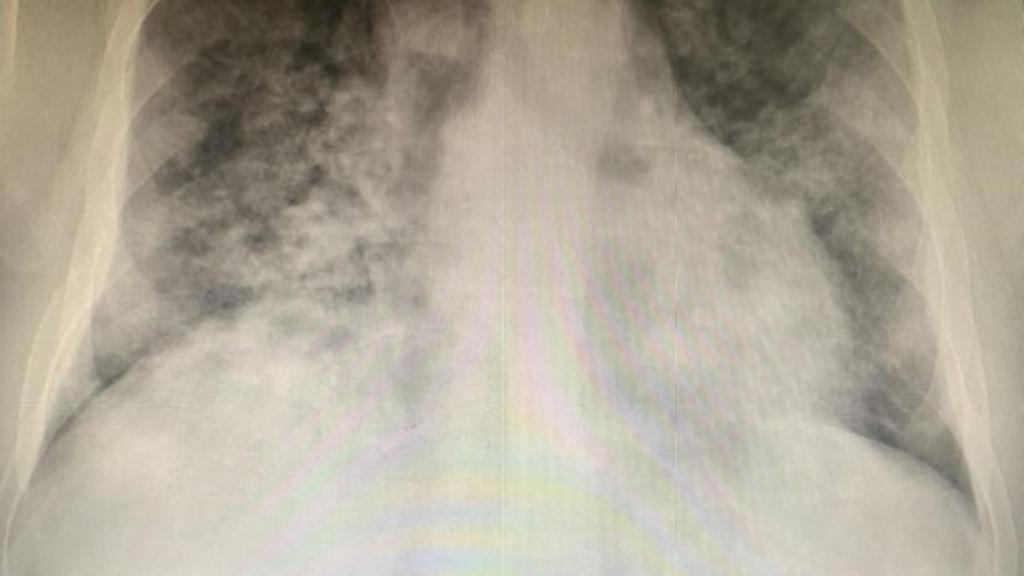

"A pesar de todo lo que llevamos ya, ayer pasé el peor momento de esta pandemia. Atendimos a Manuel, 44 años y sin ninguna enfermedad. Llevaba 6 días sintiéndose mal y 4 con fiebre. El sábado le hicieron test AG, con resultado positivo. A pesar del tratamiento la fiebre no bajaba de 39. Al llegar a Urgencias tenía 67% de saturación y 40 respiraciones por minuto", describe la situación el especialista, quien reconoce que "aunque no suelo hacerlo, le he hablado de tú. Estaba muy asustado y me ha parecido una buena forma de darle confianza".

P.D.: Sólo los nombres no son reales, el resto sí (incluida la radiografía).